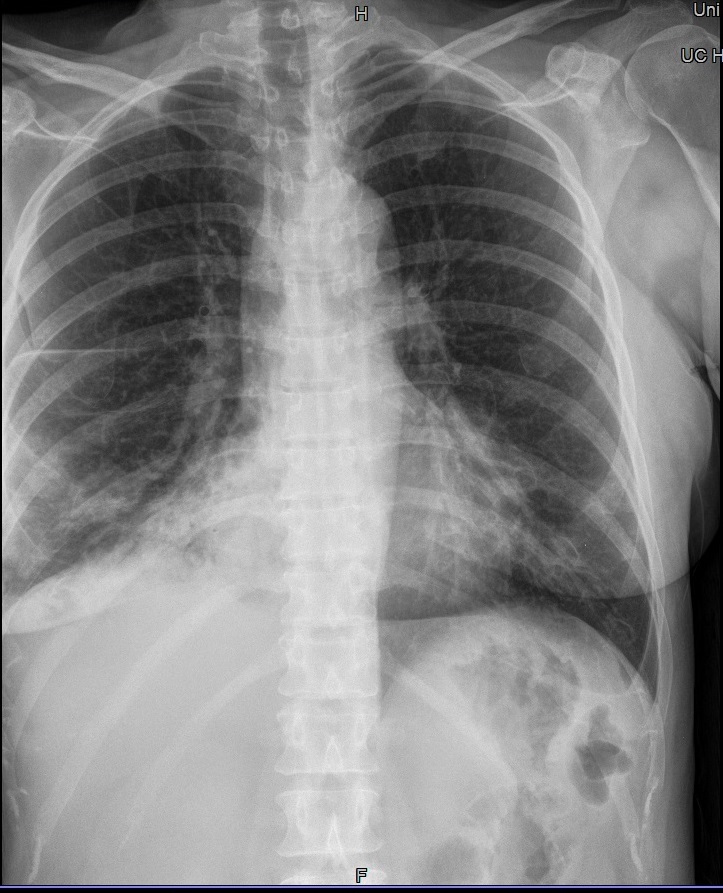

Fehler

Schneidet der seitliche Filmrand die laterale Thoraxwand ab, evtl. durch zu schmales Filmformat oder unzureichend gute Positionierung, so wird der so wichtige Thorax-Zwerchfell-Winkel (Sinus phrenico-costalis) nicht abgebildet. Eine alte oder eine kleine frische Brustfellentzündung wird auf einer solchen Aufnahme übersehen.

Abhilfe

Man muss den Patienten so stellen, dass der rechte und linke Kassettenrand noch seitlich vorstehen und die Blende nicht abschneidet.